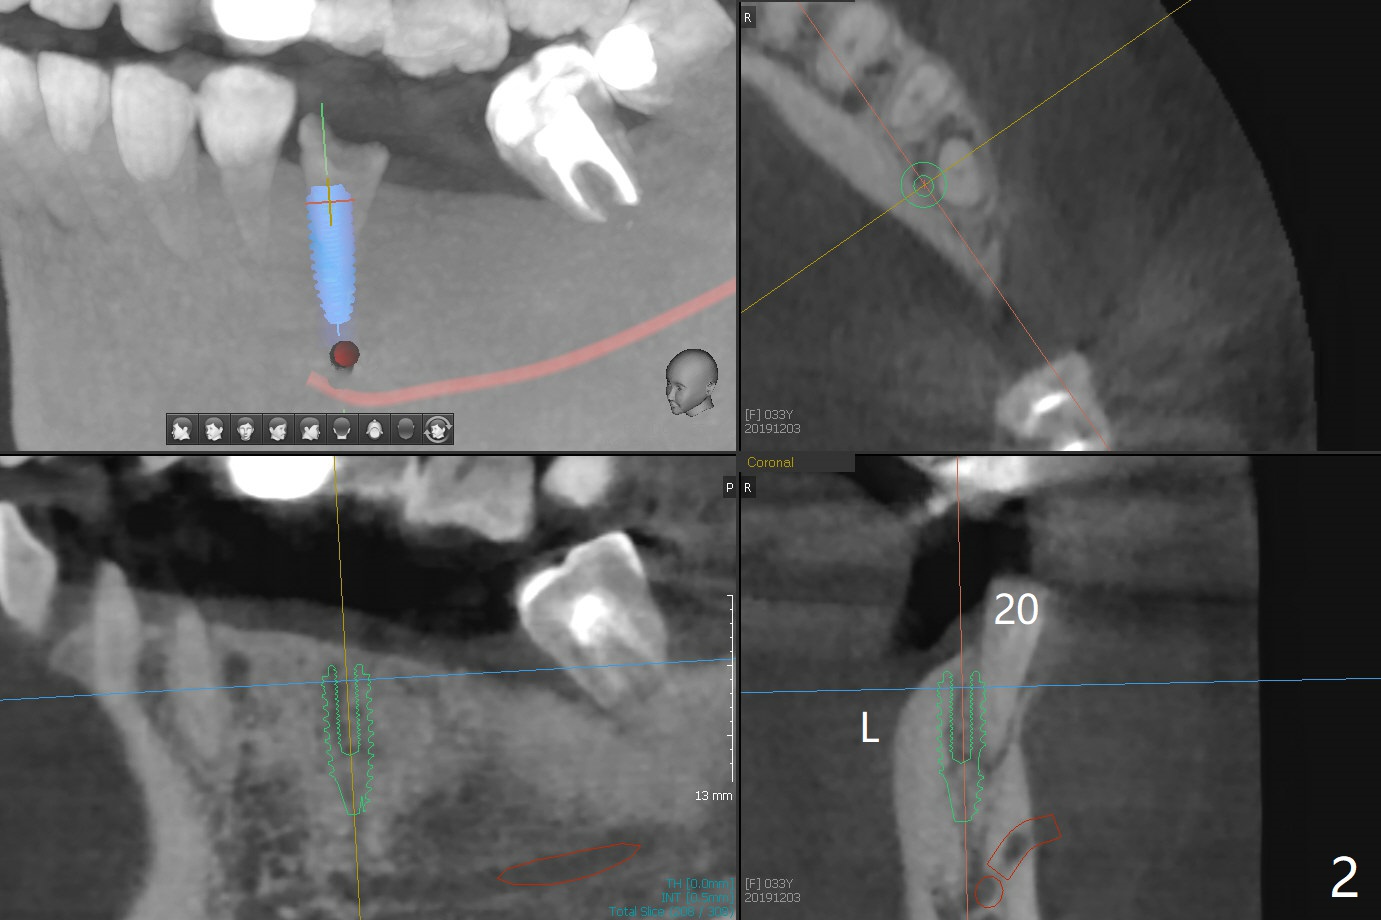

A 33-year-old woman fractures #20 equigingival with caries (Fig.1,2 barely salvageable). The ridge at #19 is atrophic (Fig.3), while the tooth #18 has mobility II (Fig.4). It seems that the best option would be extraction of #18 and 20 and immediate implant with guide (Fig.4). The tooth #20 is vital; socket shield will be conducted. To further prevent buccal plate collapse, a 3.5 or 4.0x10 mm implant will be placed lingual (Fig.2).